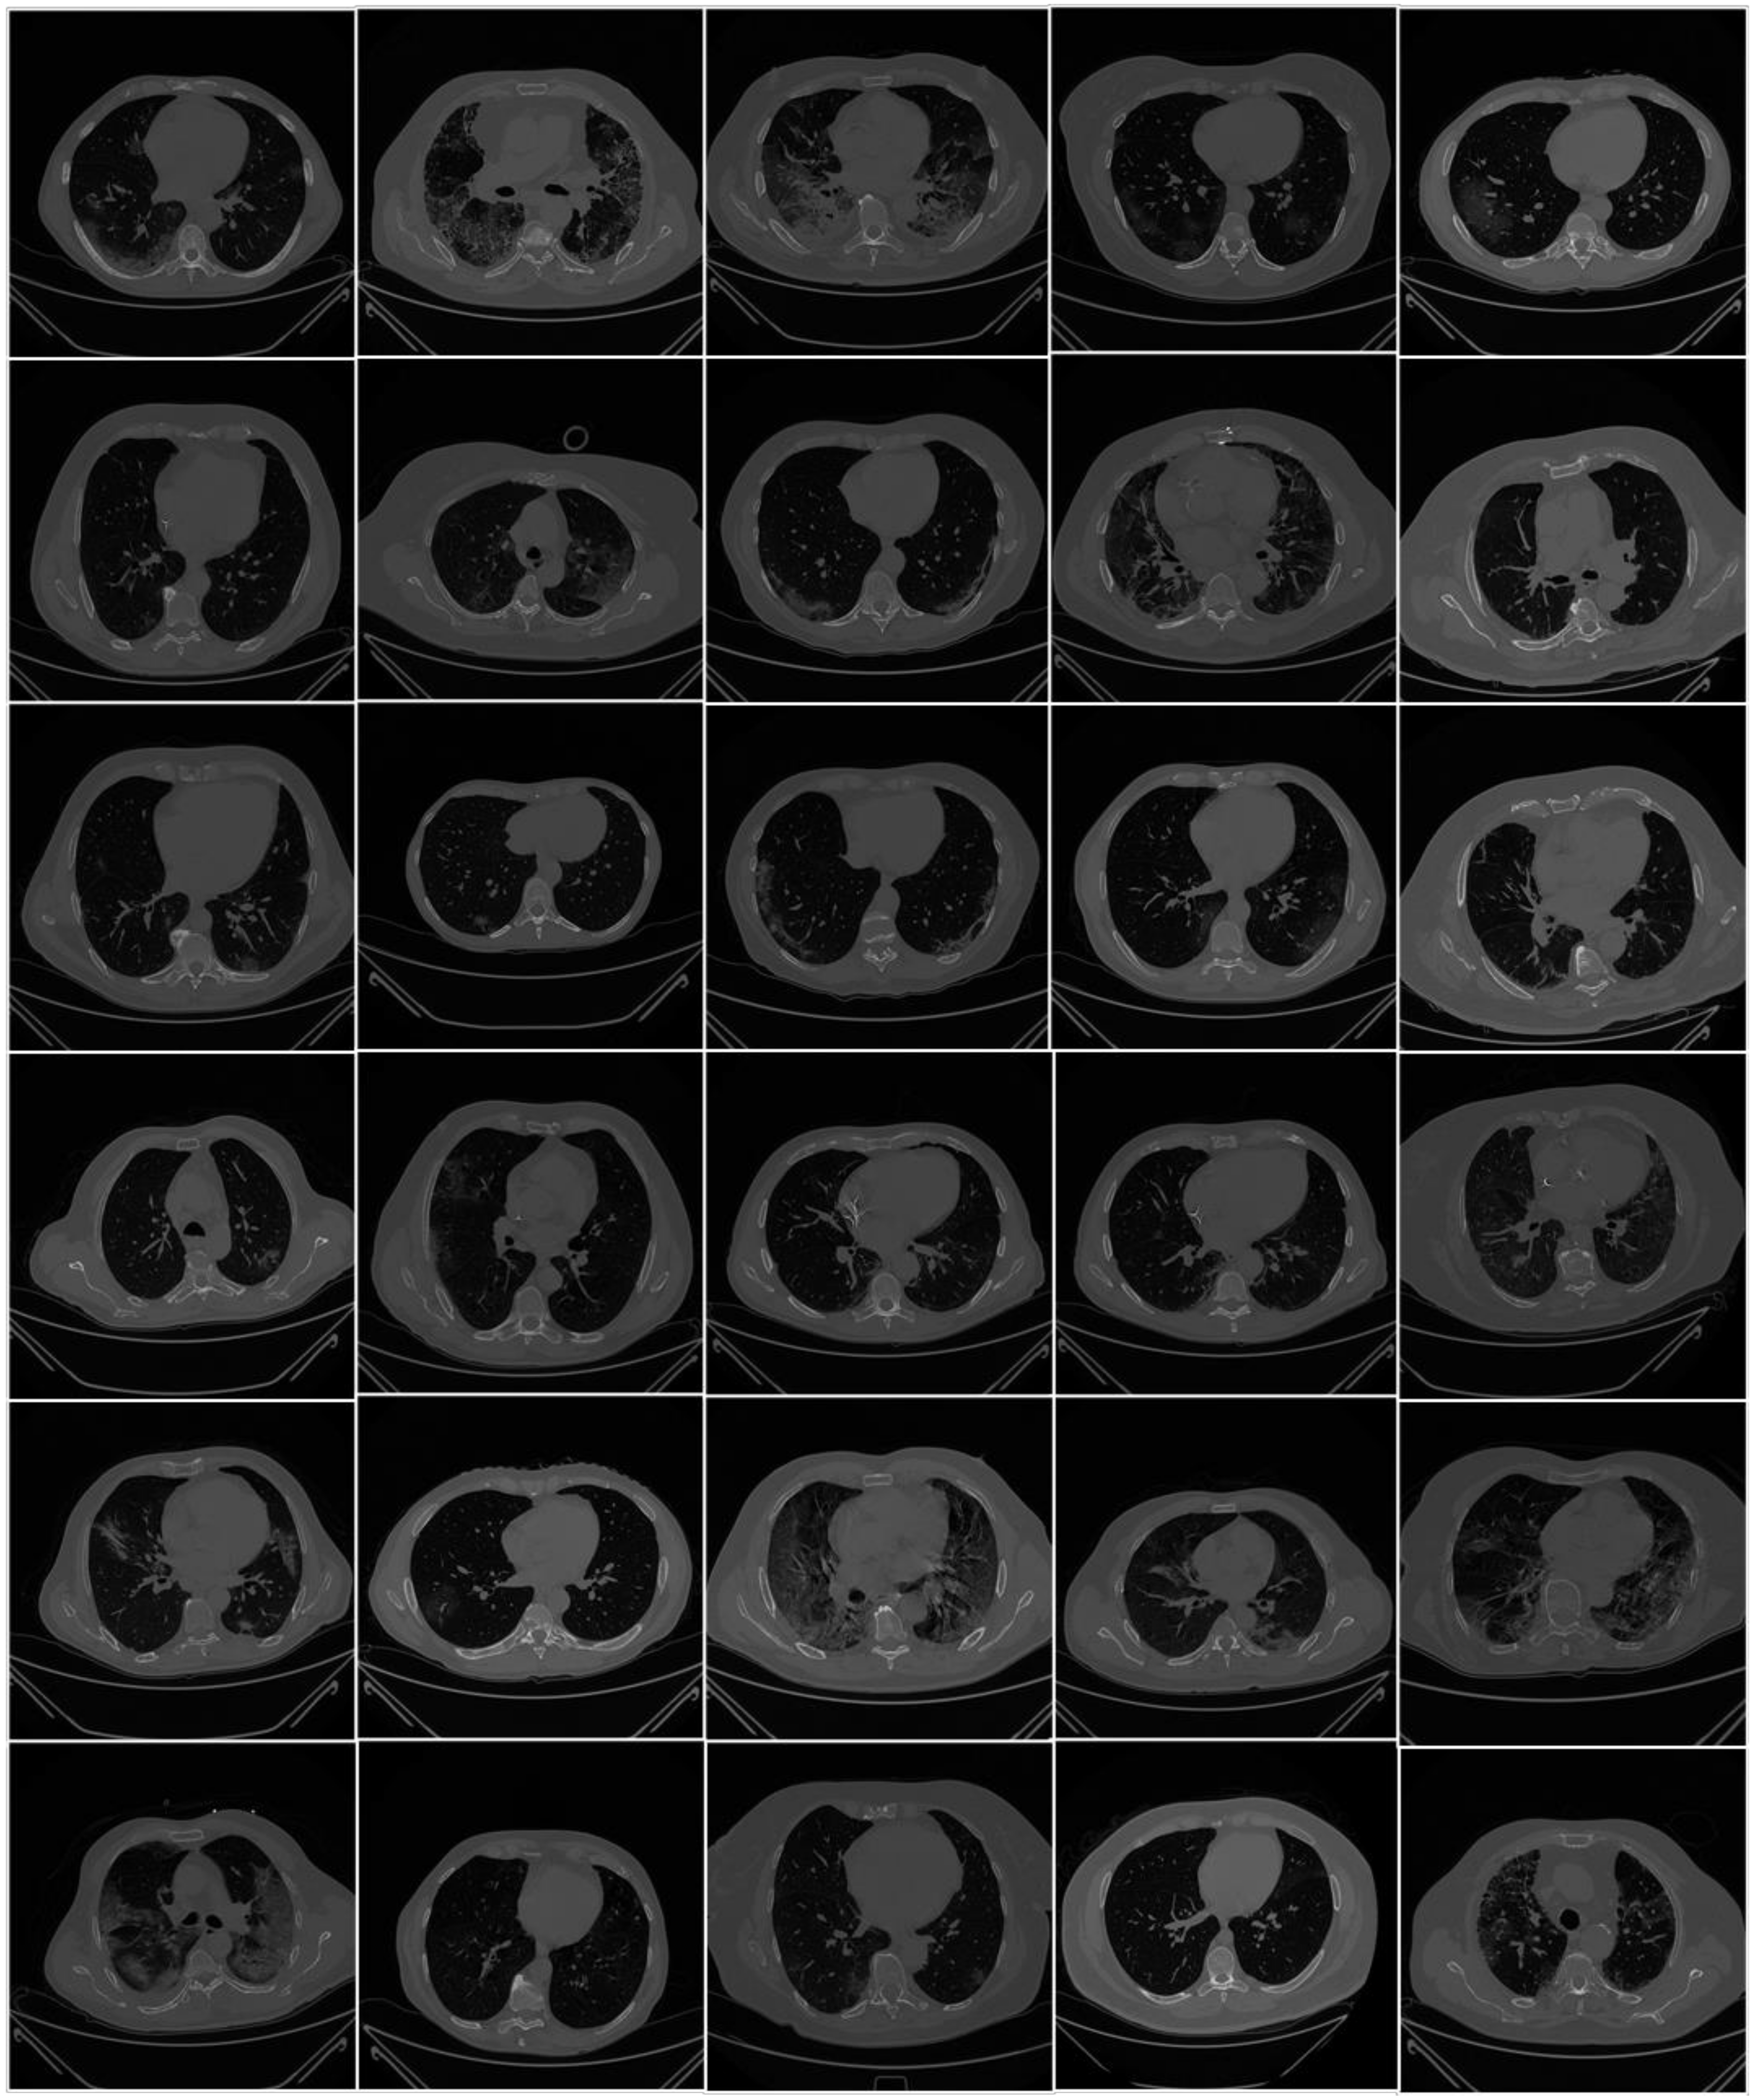

2.1.3. Data Preparation